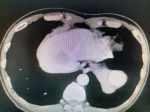

高甘油三酯血癥性胰腺炎的診治 關(guān)鍵疾病:急性壞死性胰腺炎,高甘油三酯血癥,彌漫性脂肪肝 現(xiàn)病史【一般資料】 男性,35歲,公務(wù)員 【主訴】 劇烈腹痛,惡心、嘔吐,腹脹3天。 【現(xiàn)病史】患者訴緣于3天前無(wú)明顯誘因出現(xiàn)左上腹劇烈疼痛,初為陣發(fā)性銳痛,后出現(xiàn)持續(xù)性劇痛,迅速波及全腹,并向左腰背部放射,伴惡心、嘔吐6次,嘔吐物為胃內(nèi)容物,不含血性物、蛔蟲及咖啡樣物,共吐約2000毫升左右,吐后腹痛略減輕,伴腹脹,無(wú)寒顫、高熱,無(wú)心慌氣短,無(wú)咳嗽咳痰,無(wú)尿頻、尿痛及肉眼血尿,無(wú)四肢厥冷、大汗淋漓,無(wú)黃疸,無(wú)腹瀉,可正常排氣,未排便。發(fā)病后曾于當(dāng)?shù)卦\斷為“急性胰腺炎”,予輸液治療(藥名及劑量不詳...